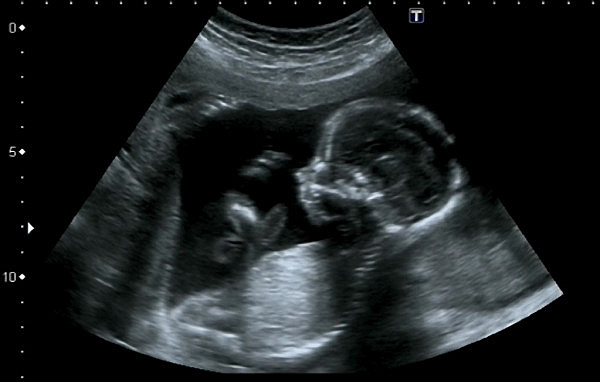

• Viabilidad

Viabilidad

El feto ya posee los organos necesarios para vivir fuera del utero materno. Se presenta un aumento rápido en la cantidad de grasa corporal Se presentan movimientos respiratorios rítmicos, pero los pulmones no están totalmente maduros,los huesos están completamente desarrollados, pero aún son blandos y flexibles

El cuerpo del feto comienza a almacenar hierro, calcio y fósforo.

• Formación del feto completa

Formación del feto completa

Para este mes el feto ya es un ser vivo y sin embargo para completar la madurez del su cuerpo en necesario que continue dentro de la encubadora natural que le proporciona la madre. Adquiere mayor peso y empieza el proceso natural para encajar y colocarse en posición.